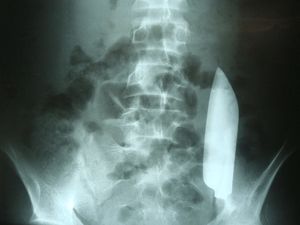

Diduga Tolak Pinjamkan Uang Buat Pelaku Tega Bunuh Ibu Kos di Medan

Polisi menduga kasus pembunuhan wanita lansia pemilik kos di Kota Medan, Sumut dipicu soal uang. Diduga pelaku kesal korban tidak mau pinjamkan uang kepadanya.